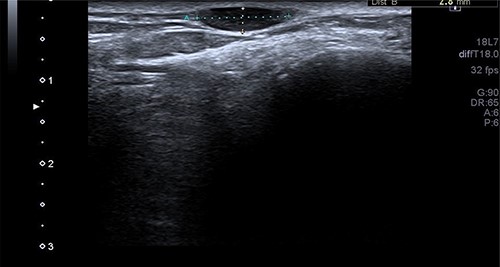

A 50-year-old lady presented to us with a lump in her left foot on the lateral aspect at the level of the calcaneocuboid joint for a 1-year duration, which was associated with pain. She consulted her GP who advised an US scan. This revealed a lump over the dorsum of the left foot on the lateral side. She also had a magnetic resonance imaging (MRI) scan which was indeterminate (Figs 3 and 4). It was reported as a suspected sarcoma. She was then referred to the Sheffield sarcoma unit where she underwent a biopsy of the swelling; which was reported as angiomyolipoma (a benign swelling). She was not keen on excision initially, but as the swelling increased in size and started becoming painful, she underwent an excision of the lesion under our care and the histopathologic examination of the excised sample confirmed it to be angioleiomyoma. The post-operative period was uneventful and she was discharged from our care after 10 weeks. At this time, she was symptom-free and had a pain score of 0/10.

T2 axial MRI image of the soft tissue lesion over the lateral foot in Patient 2 showing a lesion which is heterogeneous and slightly hyperintense to the muscle.

Similarly, in Case 2, the patient had an MRI scan which reported an indeterminate swelling suggestive of a possible sarcoma. As the MRI findings were not characteristic of the MRI findings of an angioleiomyoma, such as T1: isointense or hyperintense to muscle, T2: heterogeneous and slightly hyperintense to muscle and T1 C+ (Gd): homogenous to heterogeneous enhancement, suspicion of the sarcoma was reported from the MRI scan findings and referral to sarcoma unit was advised. This clearly shows that the US and the MRI scan findings can suggest a different diagnosis, and a confirmed diagnosis was only established following excision and histopathological examination of the excised lesion. Usually, angioleiomyomas have a peripheral low-intensity signal rim corresponding to a fibrous pseudo capsule with adjacent vascular structures with isointense or hypointense to muscle on T1 images and heterogeneous and slightly hyperintense to muscle on T2 images.